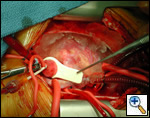

The operative approach is through a median sternotomy with the use of cardiopulmonary bypass and bicaval venous cannulation. The first dose of cold blood cardioplegia is antegrade; the remaining doses are retrograde.

High ascending aortic cannulation adjacent to the innominate artery for maximum exposure of the ascending aorta and to allow length for positioning of the patch in the ascending aorta.

One dose of antegrade cardioplegia followed by retrograde cardioplegia.

Pulmonary homograft or pericardial patches (tanned in glutaraldehyde) for the “shields”. These patches should not be too large – this will lead to aortic insufficiency.

First coronary sinus incision in noncoronary sinus to facilitate exposure of the incisions into the coronary orifice sinuses.

In most cases, the right coronary artery sinus should be opened to the left of the coronary orifice and the left coronary artery sinus to the right of the coronary orifice. Occasionally one may not have enough room between a coronary orifice and the aortic valve; in this case the incision site should be tailored to the situation.

Ensure similar orifice sizes between the proximal and distal ascending aorta after patch augmentation by the use of a sizing dilator.

Transesophageal echocardiography to assess completeness of repair, coronary blood flow postoperatively, wall motion abnormalities, and adequacy of aortic valve.